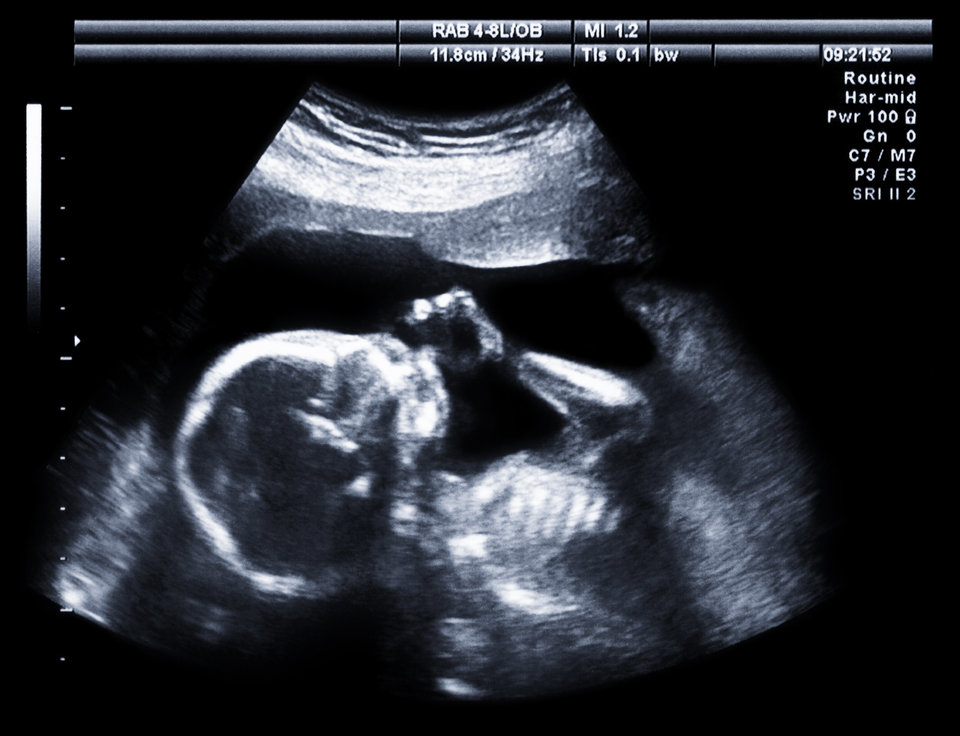

Η μεγάλη έρευνα της HuffPost για τις εξωσωματικές στην Ελλάδα

Η διαδικασία, το κόστος, οι κίνδυνοι, μέσα από προσωπικές ιστορίες και ειδικούς - της Αγγελικής Κουγιάννου

Πέρα όμως από τα στοιχεία, ας δούμε που βρίσκεται σήμερα η εξωσωματική γονιμοποίηση στην Ελλάδα. Τι διαδικασίες πρέπει να περάσει ένα ζευγάρι που αντιμετωπίζει πρόβλημα υπογονιμότητας για να αποκτήσει ένα παιδί; Πόσο θα στοιχίσει; Τι θα αντιμετωπίσει; Υπάρχουν κίνδυνοι; Πως ελέγχονται και από πότε οι Μονάδες Ιατρικώς Υποβοηθούμενης Αναπαραγωγής; Τι ορίζει το νομικό πλαίσιο και η δεοντολογία; Η HuffPost Greece πραγματοποίησε μια μεγάλη έρευνα για να βοηθήσει τα ζευγάρια να έχουν όλες τις απαραίτητες πληροφορίες, πριν προχωρήσουν σε αυτό το βήμα.